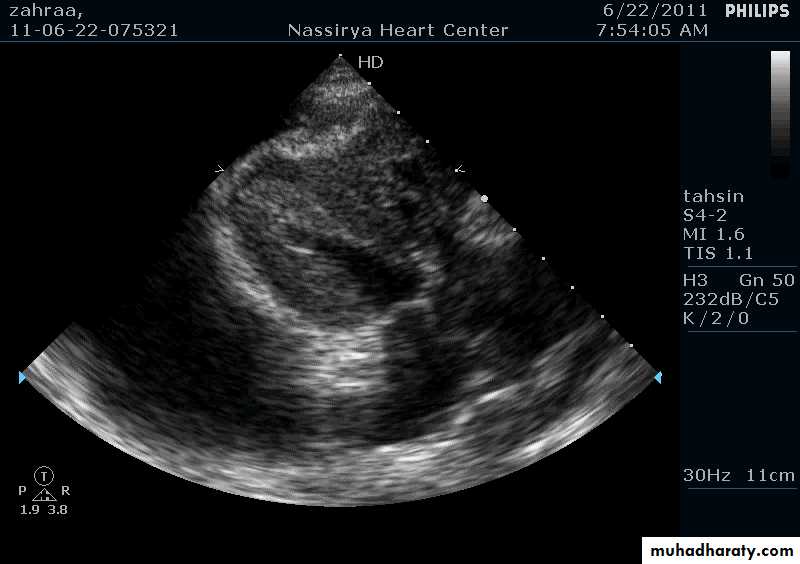

Two Dimensional Echocardiography

Ultrasound beam passing through the heart generates cross sectional images or “slices” of the heartVarious structures can be seen in real time

Two Dimensional Echocardiography indications

Assessment of LV functionDiagnosis & quantitation of severity of valvular lesions

Identification of vegetations

Identifying the source of systemic embolism

Detection of pericardial effusion